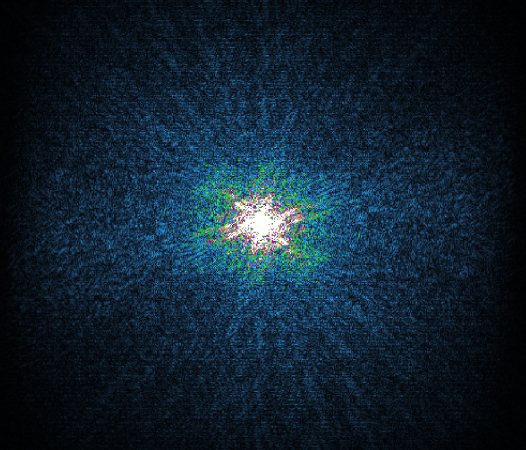

How does Compressed SENSE work?

Compressed sensing is a signal processing technique built on the fact that signals contain redundant information. In MRI this technique is used to reconstruct a full image from severely under-sampled data (in k-space) while maintaining virtually equivalent image quality.

How Philips Compressed SENSE works